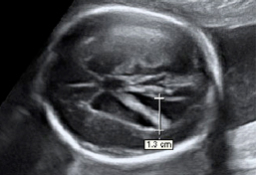

A lo largo del embarazo, el médico te recomendará una serie de pruebas diagnósticas para asegurarse que tu hijo se desarrolla correctamente, como la ecografía. Otras solo se prescriben cuando el ginecólogo sospecha que algo puede ir mal y necesita más datos para corraborarlo, como la amniocentesis o el control del bienestar fetal. Te contamos cómo y cuándo se realizan.